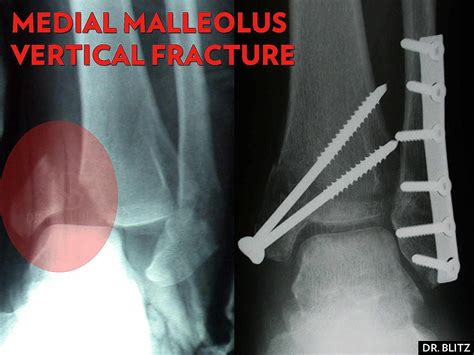

Surgical Treatment

For more severe fractures, especially those involving displacement or multiple fragments, surgery may be necessary. Surgical options include:

• Open Reduction and Internal Fixation (ORIF): This procedure involves realigning the bone fragments and securing them with plates, screws, or rods.